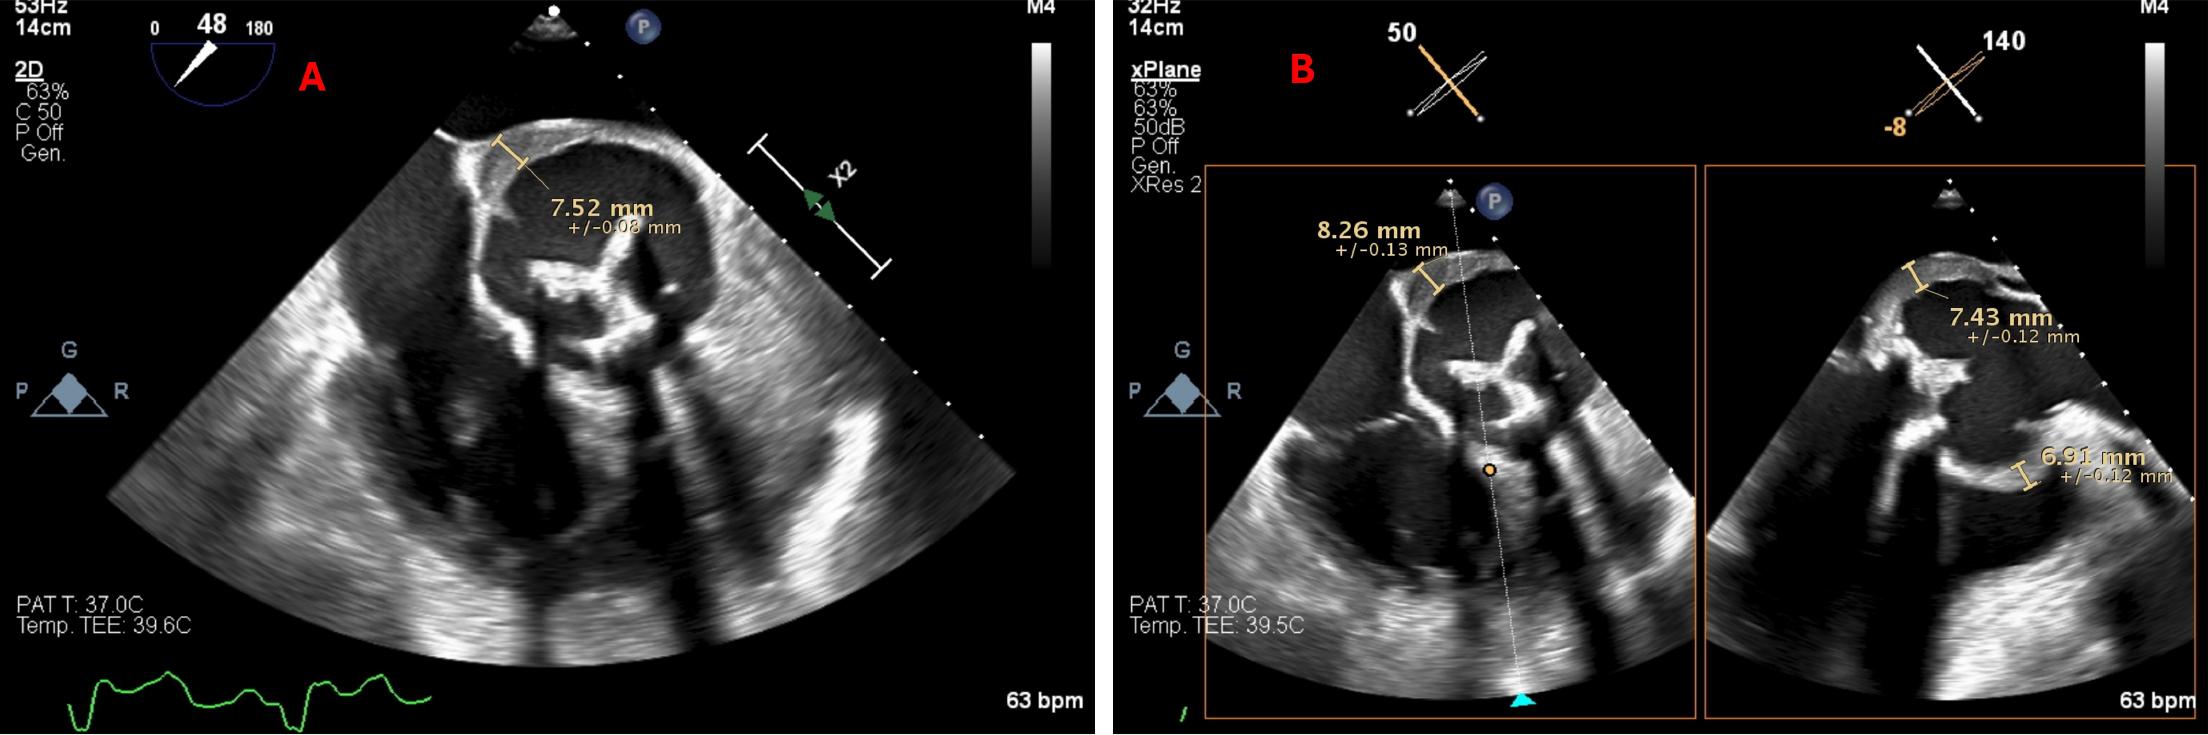

Figure 2